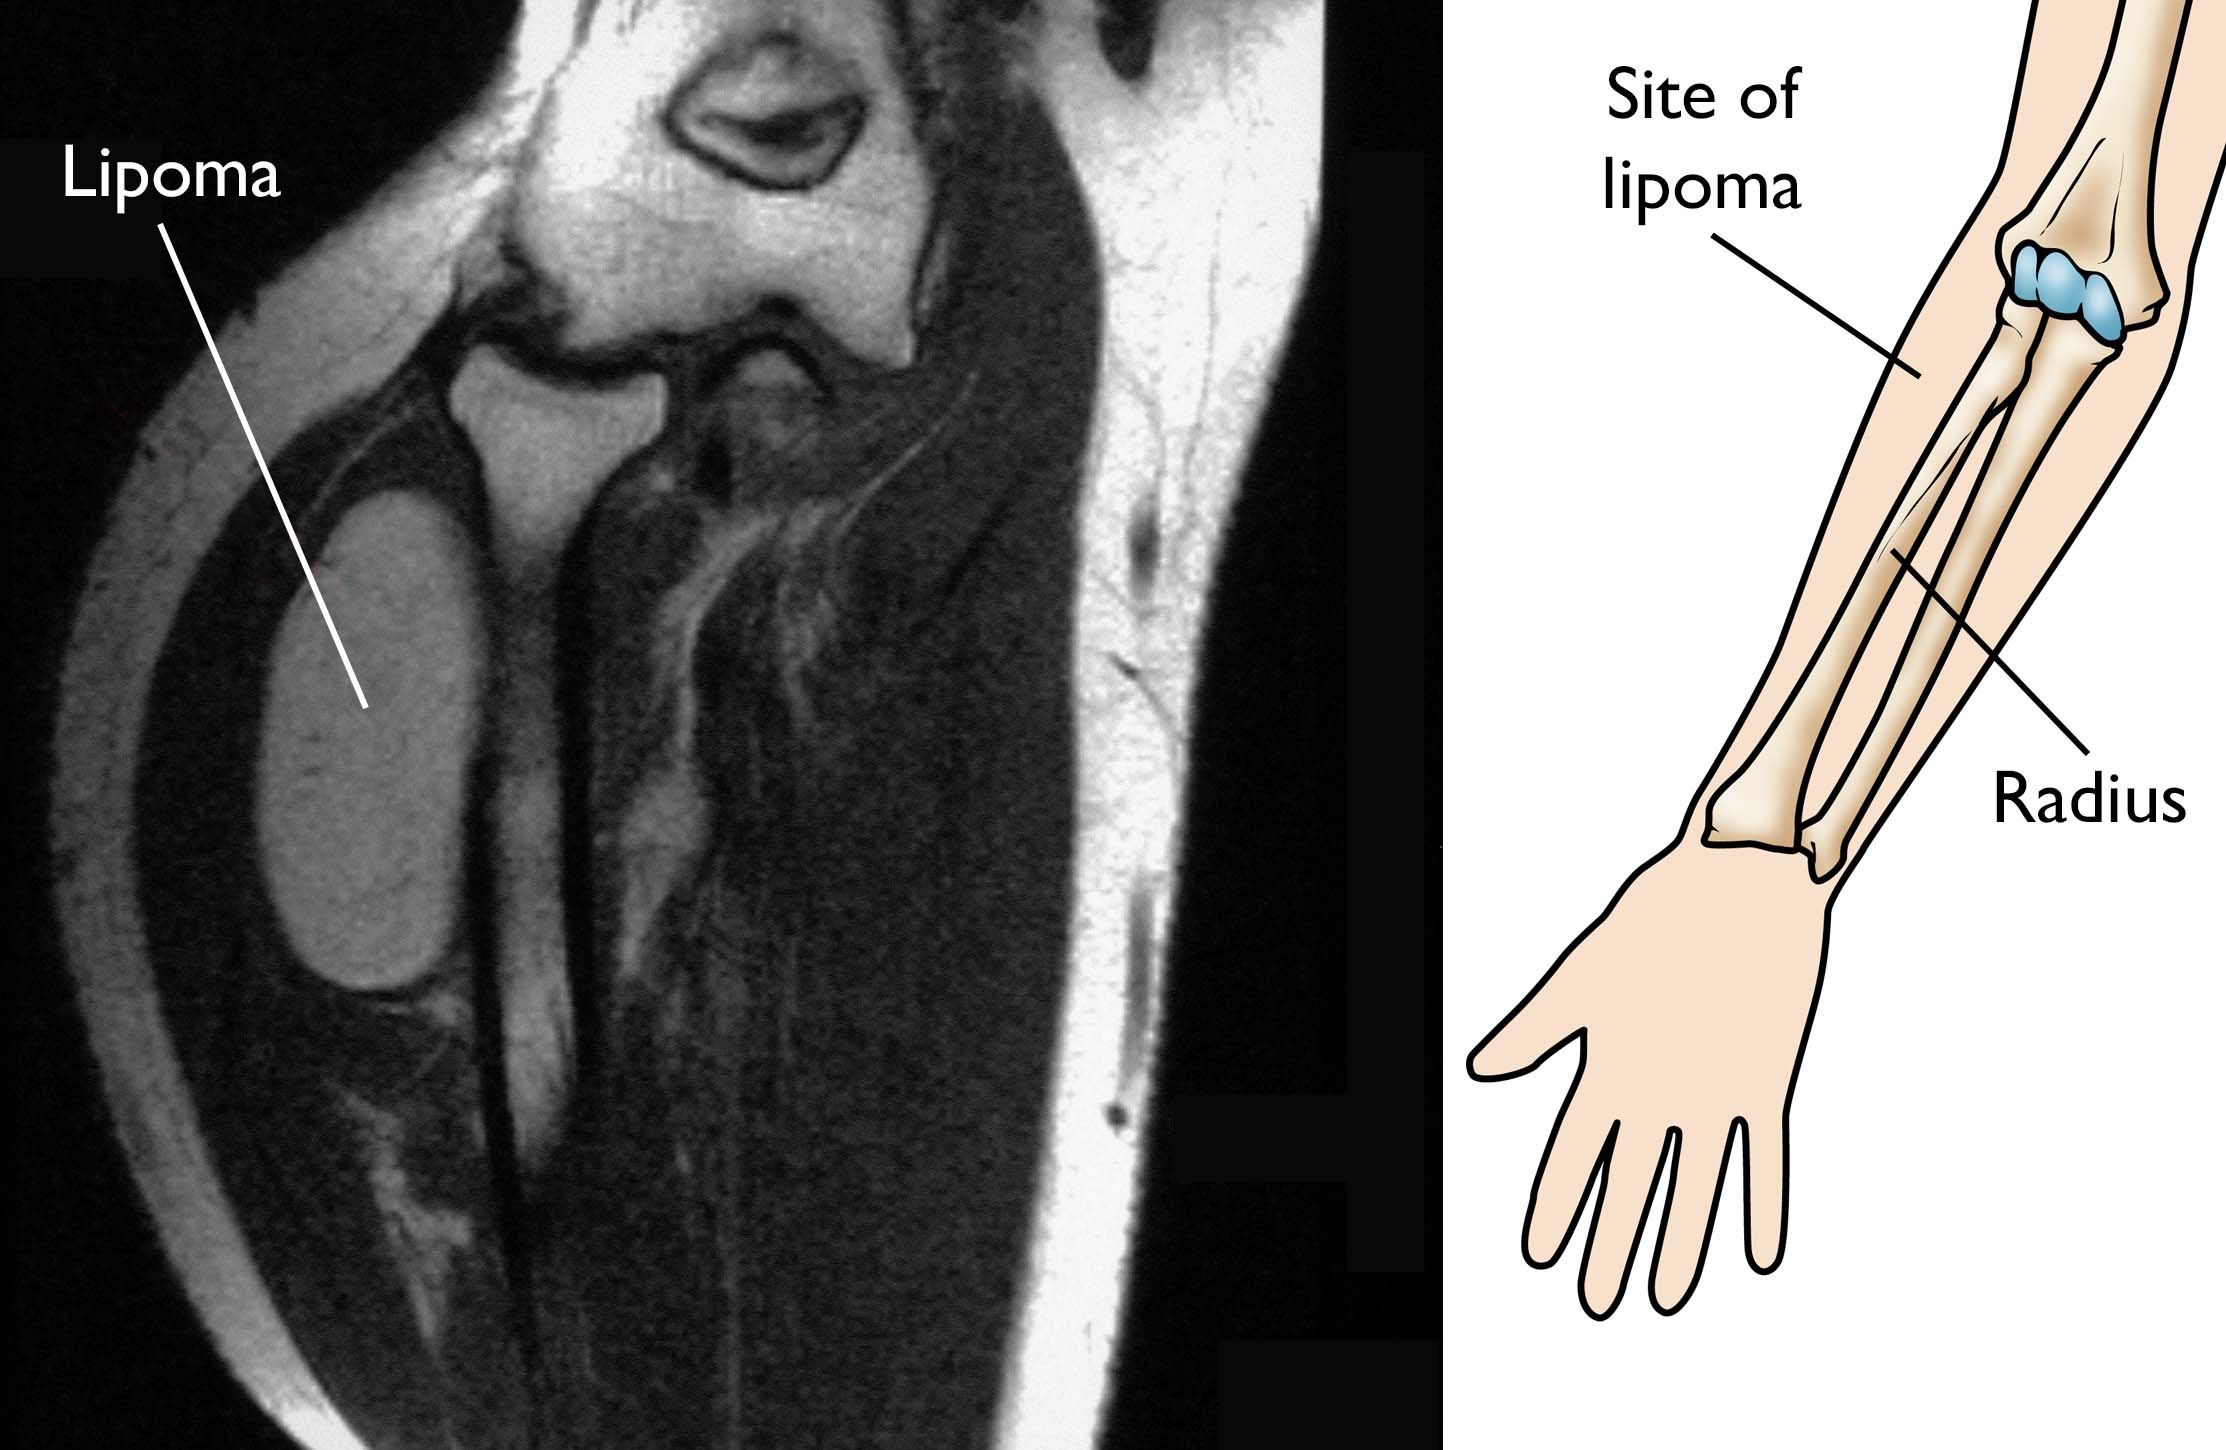

Lipoma OrthoInfo AAOS

Lipoma OrthoInfo AAOS What Is A Soft Lump On Elbow Olecranon bursitis is inflammation of the bursa in your elbow, which can cause swelling, pain, and a lump. With elbow bursitis, you may notice a squishy lump on the back of your elbow that may or may not be painful. Elbow bursitis is a soft lump at the back of the elbow that can be painful or stiff. It can. What Is A Soft Lump On Elbow.